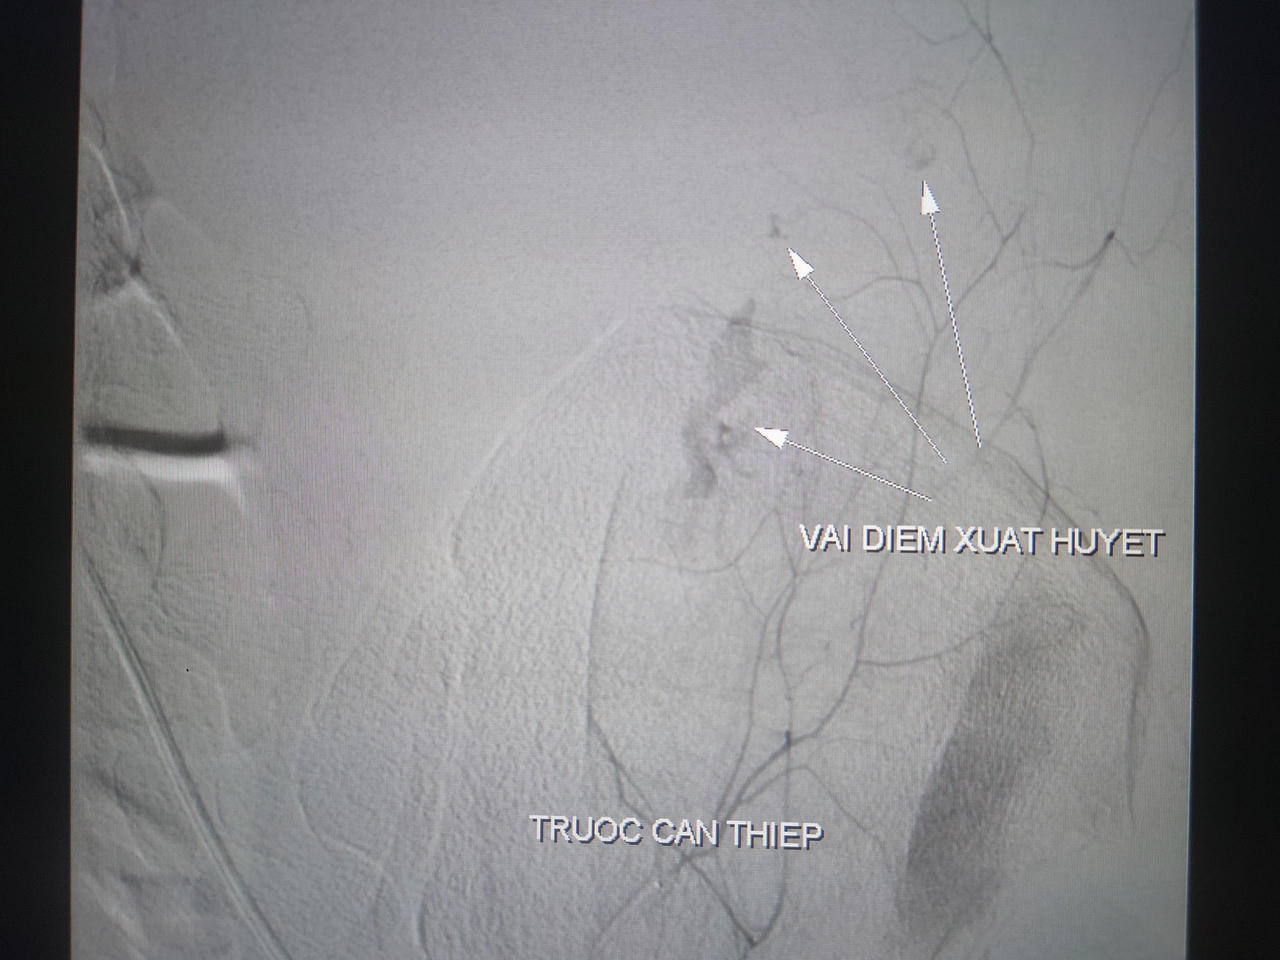

![]() |

Hình ảnh ổ xuất huyết trước can thiệp |

Bệnh nhân có chỉ định chụp và nút động mạch cầm máu các tạng số hóa xóa nền. Kết quả ghi nhận đa ổ xuất huyết xuất phát từ nhánh động mạch chậu trong trái, tiến hành bơm hỗn hợp keo.